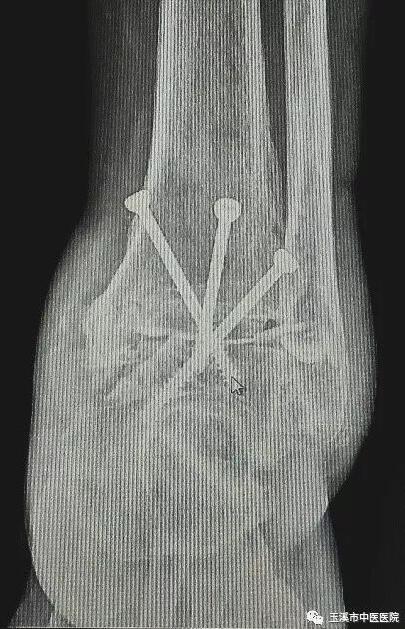

在醫(yī)務(wù)人員緊張的情況下,骨傷Ⅰ科克服種種困難,先后派出3名一線醫(yī)務(wù)人員赴千里之外的德欽縣人民醫(yī)院進(jìn)行對口援助。朱金富醫(yī)生是今年8月份去到藏區(qū)的,一到那里便積極投入工作。一位五十六歲藏族阿媽來到醫(yī)院看病時(shí),左踝關(guān)節(jié)疼痛、畸形三十余年了。 朱醫(yī)生將她收治入院,在相關(guān)檢查后,為她做了左踝關(guān)節(jié)融合術(shù)。術(shù)后藏族阿媽左踝關(guān)節(jié)功能明顯改善,生活及勞動(dòng)能力有所恢復(fù),一家人皆大歡喜。

術(shù)后X光片(左踝關(guān)節(jié)側(cè)位)